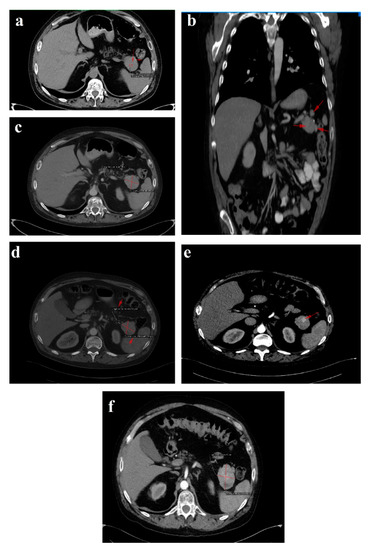

Figure 3. 1 February 2018 CT scan: (a) axial image without contrast showing a round solid mass with microcalcification in the tail of the pancreas; (b) arterial phase coronal reconstruction showing a hypervascular mass with satellite nodules situated in the pancreatic tail; and (c) axial image, arterial phase showing a 35/44 mm tumor in the pancreatic tail. September 2018 follow-up CT: (d) axial image, arterial phase showing stable disease. October 2019 follow-up CT: (e) axial image, arterial phase showing inhomogeneous contrast enhancement and small-scale tumor progression. July 2020 follow-up CT: (f) axial image, arterial phase showing evident tumor mass progression.

In February 2018, upon presentation to our department of endocrinology, the clinical examination revealed a middle-aged male patient unable to walk unassisted or without a frame, with severe bilateral hip arthralgia, slightly elevated blood pressure (150/90 mmHg) and tachycardia (heart rate = 110 bpm). The laboratory tests revealed normocytic normochromic anemia (Hb = 11 mg/dL), hypoproteinemia (5 g/dL), elevated inflammatory markers (ESR = 91 mm/h, fibrinogen = 668 mg/dL, high sensitivity CRP = 73.7 mg/L), high glycated hemoglobin (HbA1c = 7.6%), normal chromogranin A (CgA) and 5-hydroxyindoleacetic acid (5-HIAA), and elevated plasma glucagon levels (2130 ng/L, N < 209) that confirmed the positive diagnosis of glucagonoma syndrome. Biochemical screening for MEN 1 syndrome was negative (serum calcium = 8.3 mg/dL, PTH = 32.62 pg/mL, 25 hydroxy vitamin D = 27.27 ng/mL, prolactin = 12 ng/mL, IGF1 = 114 ng/mL). A multiphasic contrast-enhanced CT diagnosed a 35/44 mm tumor with heterogenous texture located in the pancreatic tail, multiple peritumoral nodules suggestive of locoregional metastases, two incompletely consolidated fractures at the sixth and seventh ribs, and a reduction in bone density and the height of the thoracolumbar vertebras (Figure 3a–c).

Tc-99m-methylene diphosphonate (MDP) bone scintigraphy indicated an abnormally high accumulation of the radiotracer throughout thoracolumbar spine and focal in the right scapula, C5 and C9 right ribs, C12 left rib, L2 vertebra and the left femoral head. The case was rediscussed in our MDT and pancreatic surgery was postponed for further investigations. The glucocorticoid treatment was tapered down and ultimately interrupted, and long-acting SSA therapy with lanreotide Autogel 120 mg every 28 days was started. In a matter of weeks, the NME lesions and diarrhea waned, and the biochemical parameters improved. The glycemic targets were easily achieved with low dosages of long-acting insulin (HbA1c = 6.1%), the inflammatory syndrome ameliorated (ESR = 30 mm/h, fibrinogen = 479 mg/dL) and plasma proteins returned to their normal range (6.4 g/dL).

The six month follow-up in September 2018 was uneventful, with the glucagonoma syndrome well controlled on SSA therapy, normal plasma CgA, decreasing glucagon levels (863 ng/L) and stable disease on CT (Figure 3d). It is important to mention that the patient received treatment with vitamin K antagonists for the deep vein left leg thrombosis and displayed high fluctuations in INR values. Despite our plan for the tumor surgical resection, the preoperative biological check-up revealed an INR value of 14, which prompted intravenous phytonadione administration. The INR reached the therapeutic range; however, the patient developed sagittal sinus thrombosis that was eventually favorably managed by the department of neurology.

In October 2019, a follow-up abdominal multiphasic contrast-enhanced CT showed small-scale tumor progression and the patient was scheduled for surgery again (Figure 3e). The echocardiography performed during the preoperative cardiologic evaluation revealed hypokinesia of the ventricular septum; akinesia of the basal segment of the inferior wall; akinesia of the medium segment of the inferolateral, lateral and anterior walls; and severe left ventricular dysfunction with an ejection fraction of 28%. Coronary angiography uncovered trivascular atherosclerotic disease, and a percutaneous angioplasty with stent implantation was performed. The surgical intervention was postponed again.

Regrettably, in the spring of 2020 the COVID-19 pandemic reached our country and follow-up was possible only in July 2020, when, despite clinical control, the tumor (52/45 mm) and the peritumoral nodules had progressed; however, no hepatic or bone metastases were detected during morphological imaging (Figure 3f). As expected, we attempted surgery once more. This time, the patient was infected with SARS-CoV-2 and, by an unexpected fortunate chance, he had a completely asymptomatic infection.

In January 2021, a follow-up CT reconfirmed locoregional tumor progression without apparent distal metastasis (Figure 6a–c), and a distal pancreatectomy and splenectomy were performed with a favorable outcome. An open approach with a bilateral subcostal incision was chosen. After opening the abdomen, a thorough examination of the peritoneal cavity was performed. We discovered a 6/5 cm tumor in the tail of the pancreas, without any vascular or retroperitoneal involvement. No liver or peritoneal metastases were present. We opted for a distal spleno-pancreatectomy in a standard fashion with a clockwise approach and individual splenic artery and vein ligation, ensuring a proper oncological safety margin on the pancreatic body. The pancreas was transected using monopolar cautery (Figure 7a) with pancreatic duct identification and clipping (Figure 7b), and the pancreatic stump was double sutured: the first was an overlapping horizontal mattress suture, and the second was a figure-eight suture (Figure 7c). Two drainage tubes were placed, the abdomen was closed, and the specimen was sent for pathology examination (Figure 7d). The postoperative course was uneventful. We checked the amylase level in the drained fluid on the third postoperative day and it was normal, which allowed us to exclude the pancreatic fistula. The abdominal ultrasonography performed did not show any collections, and the drainage tubes were removed. The patient was discharged on the eighth postoperative day.